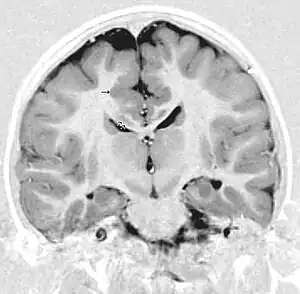

Polymicrogyria can lead to similar conditions that are linked to ulegyria such as mental retardation, cerebral palsy, and epilepsy. It has been observed that patients with polymicrogyria are not receptive to epilepsy surgery. However, responses of patients with ulegyria to similar surgeries are still not fully known, which makes distinction of these two disorders significant. In vivo neuroimaging techniques, namely MRI, have been instrumental in making this distinction. An MRI image of ulegyria is identified by mushroom shaped gyri, deformities in white matter, and localization mainly in the posterior cerebral region.[1] Polymicrogyria is typically recognized by a scalloped appearance at the bordering region between grey and white matter.[18] Although these distinctions have been made with many patients, there is still some difficulty in defining distinct boundaries between these two similar conditions.[7]

Primarily, the main method of detecting ulegyria is through the use of MRI screening for epilepsy. Normally an MRI of an ulegyria affected region will reveal groups of deteriorated neurons with gliosis present. In addition, unaffected gyri are also present in especially bilateral watershed regions indicating delayed effects of perinatal hypoxic damage.[4] However, there are three main criteria for diagnosing ulegyria using MRI in addition to the features mentioned above:[4]

- 1.The presence of a poorly demarcated lesion

- 2. Atrophy and thinning of the cortex resulting in the characteristic “mushroom” like shape of ulegyria.

- 3. Presence of white matter signal abnormalities as a result of FLAIR signaling (fluid attenuated inversion recovery).

Another sign of ulegyria that is visible on an MRI scan is the presence of a widened subarachnoid space, signifying cortex atrophy. FLAIR signaling can help visualize the depths of the parietal-occipital sulci, which also allows ulegyria-affected gyri to be identified.[6] Though there is still confusion in differentiating ulegyria and polymicrogyria in patients, MRI allows for the proper identification in the majority of the cases. In addition, most of the current research regarding ulegyria is focused on improving this identification. Furthermore, MRI can diagnose whether ulegyria presence is unilateral or bilateral.[1] Electroencephalography, EEG, can also be used to screen for ulegyria, though MRI is still preferred. This is mainly done for epilepsy patients as abnormalities in EEG recordings indicate the presence of ulegyria in the area of the brain being tested.[7] For example, when EEG tests in epileptic patients show deviations in the frontal and central-parietal regions, ulegyria can be considered to be present in that area.[7]